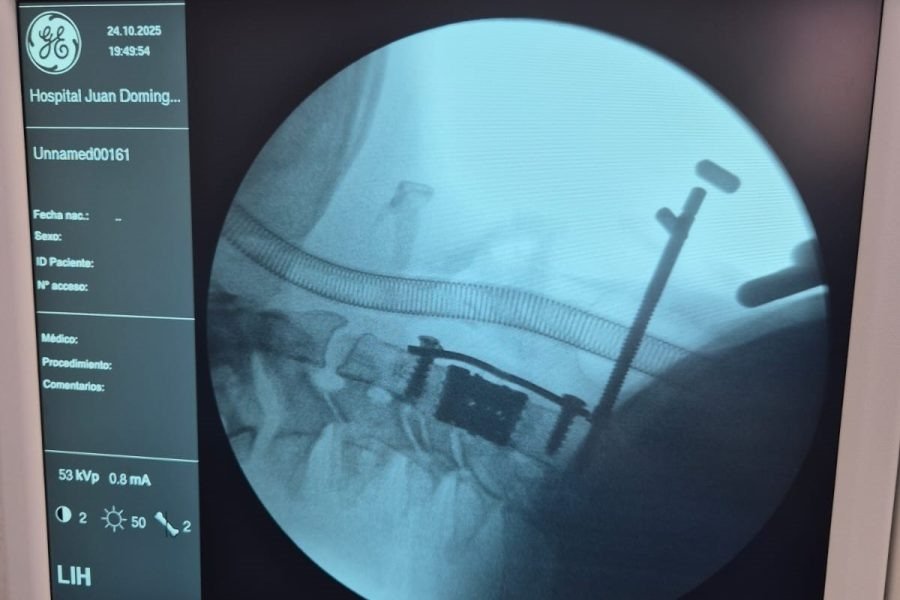

La intervención consistió en una corpectomía cervical, técnica quirúrgica destinada a resolver cuadros severos de compresión medular o radicular mediante la extracción del cuerpo vertebral afectado y su reemplazo por una prótesis especialmente diseñada, provista por el ministerio de Salud, a través de las empresas Zion–Corpomedica.

La corpectomía cervical es una práctica de alta complejidad que requiere precisión milimétrica y equipamiento de última generación. A través de una vía anterior en el cuello, se extrae uno o más cuerpos vertebrales y se reconstruye la estructura ósea mediante injerto o prótesis, liberando la presión sobre la médula espinal.